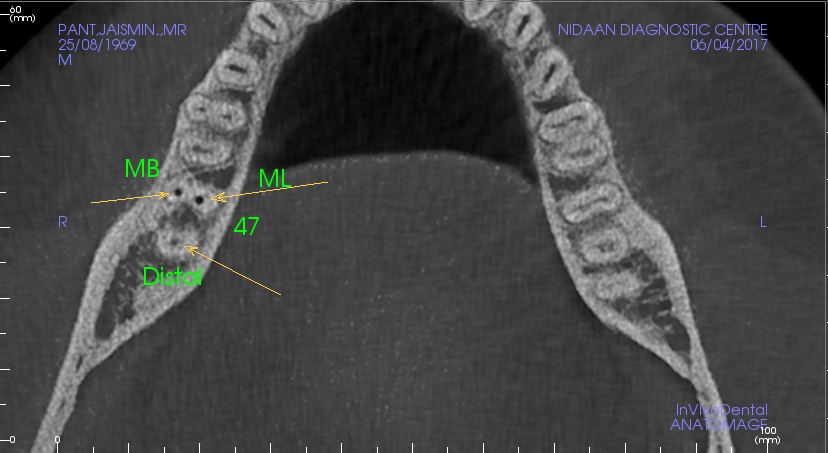

Endodontic Assessment

Impacted Tooth